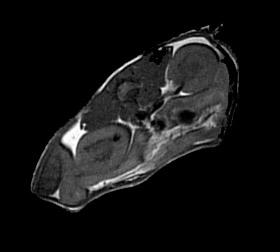

K1‑dagen ble gjennomført med et sterkt faglig program som viste bredden i instituttets virksomhet. PhD‑sesjonen bød på solide presentasjoner som illustrerte spennvidden i forskningen ved K1. I undervisningsdelen fikk vi vite mer om Vestlandslegen fra både et makro- og et mikroperspektiv, og foredraget om menneskelig og kunstig intelligens var et fint avbrekk som ga tid til refleksjon. I innovasjonsbolken fikk et godt innblikk i nye forsknings- og utviklingsmiljøer ved instituttet, før dagen ble avrundet med viktige perspektiver på samarbeid mellom UiB og HUS. Middagen som fulgte ble også meget hyggelig. Det var en anledning til å snakke sammen i et roligere tempo og møte «nye» kolleger på tvers av fagmiljøene, uten program og tidsrammer. Tusen takk til alle involverte og inverterte som bidro til at dagen ble så bra som vi hadde håpet.

Les mer for å se bilder fra K1-dagen.